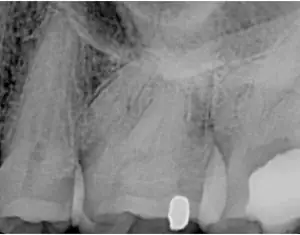

A patient came in with pain in tooth No. 18. It had a history of a small crack that resulted in needing a root canal.